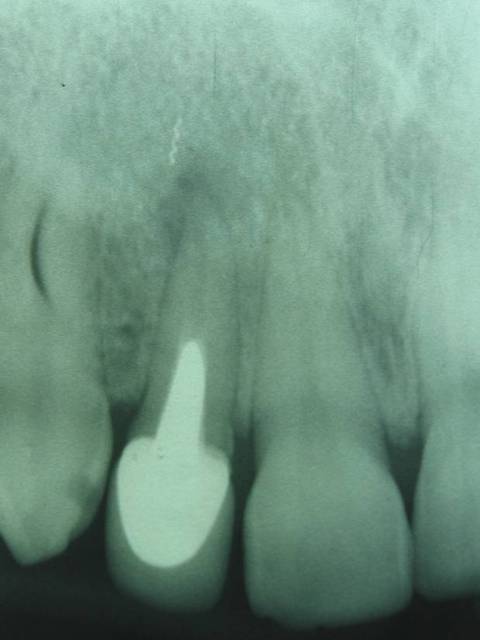

Cas déja posté. F2 neuf cassé dans un canal DL de 36 suite à une petite précipitation à la fin de l'endo.

Dommage car quand on voit la préop et les calcifications, on pouvait se dire que j'avais fait le plus dur.